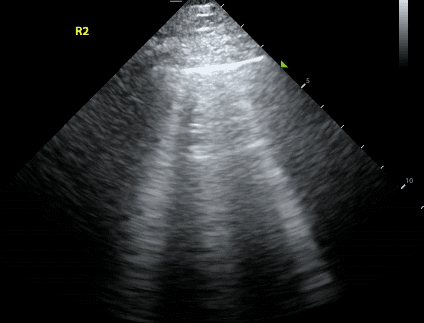

B lines are vertical hyperechoic artifacts originating from the pleural line that look similar to comet-tails. The artifact that generates B lines is the ‘ring down’ artifact.

B lines occur due to thickening of the interlobular septa, which are sheet-like structures that surround pulmonary lobules. Thickening can be due to fluid (eg. pulmonary edema, pulmonary hemorrhage), collagen fibrous tissue, or cells (eg. interstitial lung disease, sarcoidosis).

B lines are considered pathologic when there are three or more B lines in one rib space.